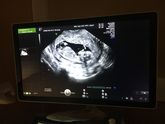

13 мая 2022 16:05 Блин, третья беременность а живот на 6 недели вылез, конечно я понимаю что это не беременный живот а мои ослабленные мышцы и жир. Сама я не худая. Но приходится втягивать живот максимально. Вроде можно раслабится типо если спросят беременна то дааа но … Читать далее